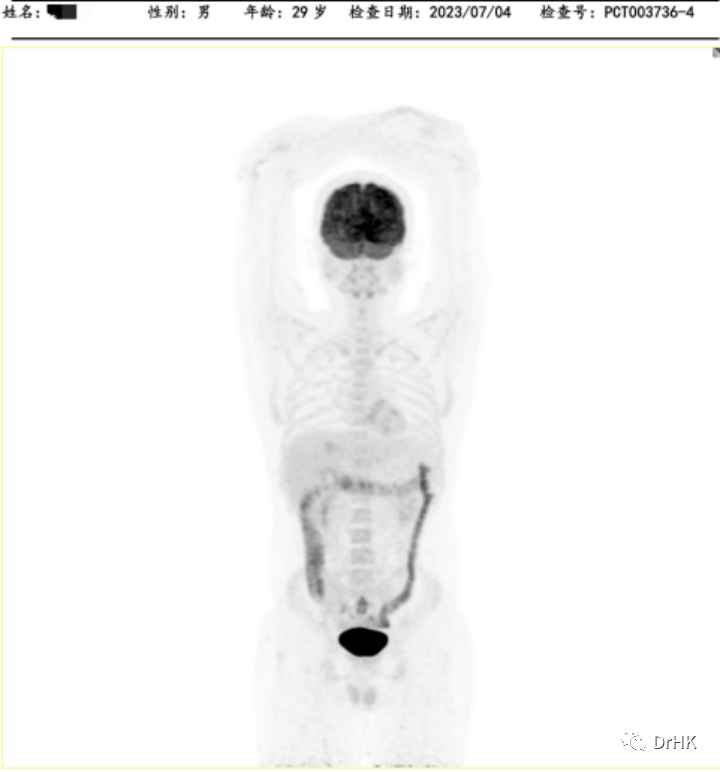

第一步治疗目标实现后,按计划开始了二次自体移植联合 CAR-T 细胞治疗的巩固治疗。本次我们采用了 TEAM 方案作为预处理(噻替哌+依托泊苷+阿糖胞苷+马法兰),并制备回输了 CD19/CD20 双靶点 CAR-T。治疗过程比较顺利,回输 CAR-T 细胞后 d5 天起开始出现发热,d8 天体温最高 39℃,诊断细胞因子释放综合征,判定 CRS 分级 I 级,ICANS 分级 0 级。检测到 CART 的扩增,患者粒细胞于自体造血干细胞回输后第 14(2022-07-05)天植活,血小板于自体造血干细胞输注后第 12 天(2022-07-03)植活。移植后我们给予患者口服奥布替尼作为维持治疗。

随后患者定期随访,分别于移植后半年、一年完善影像学评估。PET 如下图所示: